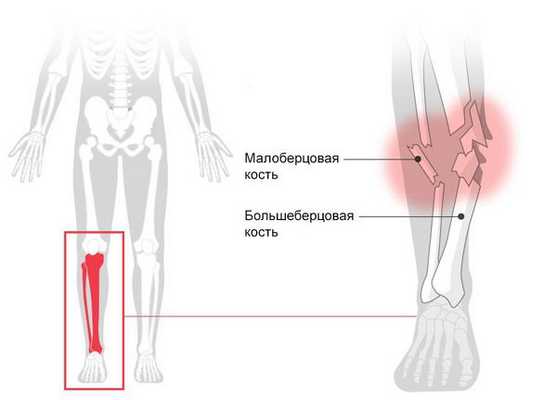

Перелом голени (Fracture of lower leg) — это нарушение целостности большеберцовой или малоберцовой кости. При переломе человек не может опереться на ногу, возникает острая боль, меняется длина и конфигурация голени [1] .

При переломе голени нередко повреждается несколько костей, например:

- при автодорожной аварии перелом центральной части большеберцовой кости часто сочетается с травмой верхнего конца малоберцовой кости;

- падение с большой высоты может привести к перелому нижнего конца большеберцовой кости и наружной лодыжки.